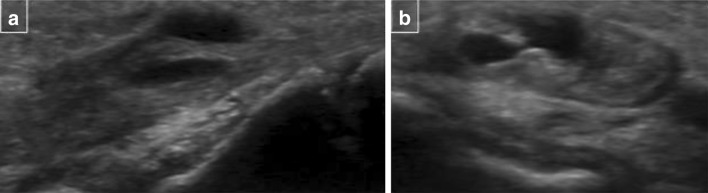

Sonographic examination of the mass revealed a focal partial thickness longitudinal defect of the extensor digitorum tendon of the middle finger, this communicated with an intratendinous cystic lesion arising from the dorsal aspect of the extensor digitorum tendon of the right middle finger. The lesion measured 7 × 5 × 8 mm, it was thin walled, cystic and did not demonstrate any intrinsic flow on Doppler. The lesion had posterior acoustic enhancement. It moved with the tendon on both active and passive movements of the middle finger. There was no tenosynovitis and remaining extensor tendons were normal. The appearances were consistent with a small focal tear and associated intratendinous ganglion of the extensor digitorum tendon of the right middle finger (Figs. 1, 2).

Fig. 1.

Longitudinal (a) and transverse (b) sonographic images of dorsum of the hand demonstrate a ganglion within the extensor tendon of the middle finger